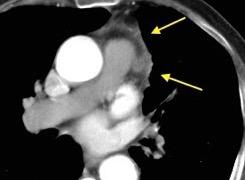

Nódulos pulmonares múltiples. (flechas verdes). Masas paratraqueales. (flechas amarillas). Dudoso ensanchamiento retrocrural (flechas negras). sigue….

T. mixto de células germinales del testículo

izquierdo Metástasis pulmonares. (flechas verdes). Ganglios paratraqueales. (flechas amarillas). Ganglios retroperitoneales (flechas negras)

Tawfik A et al. Trans-diaphragmatic Pathologies: Anatomical Background and Spread of Disease on cross-sectional Imaging. Current Problems in Diagnostic Radiology. 2021.